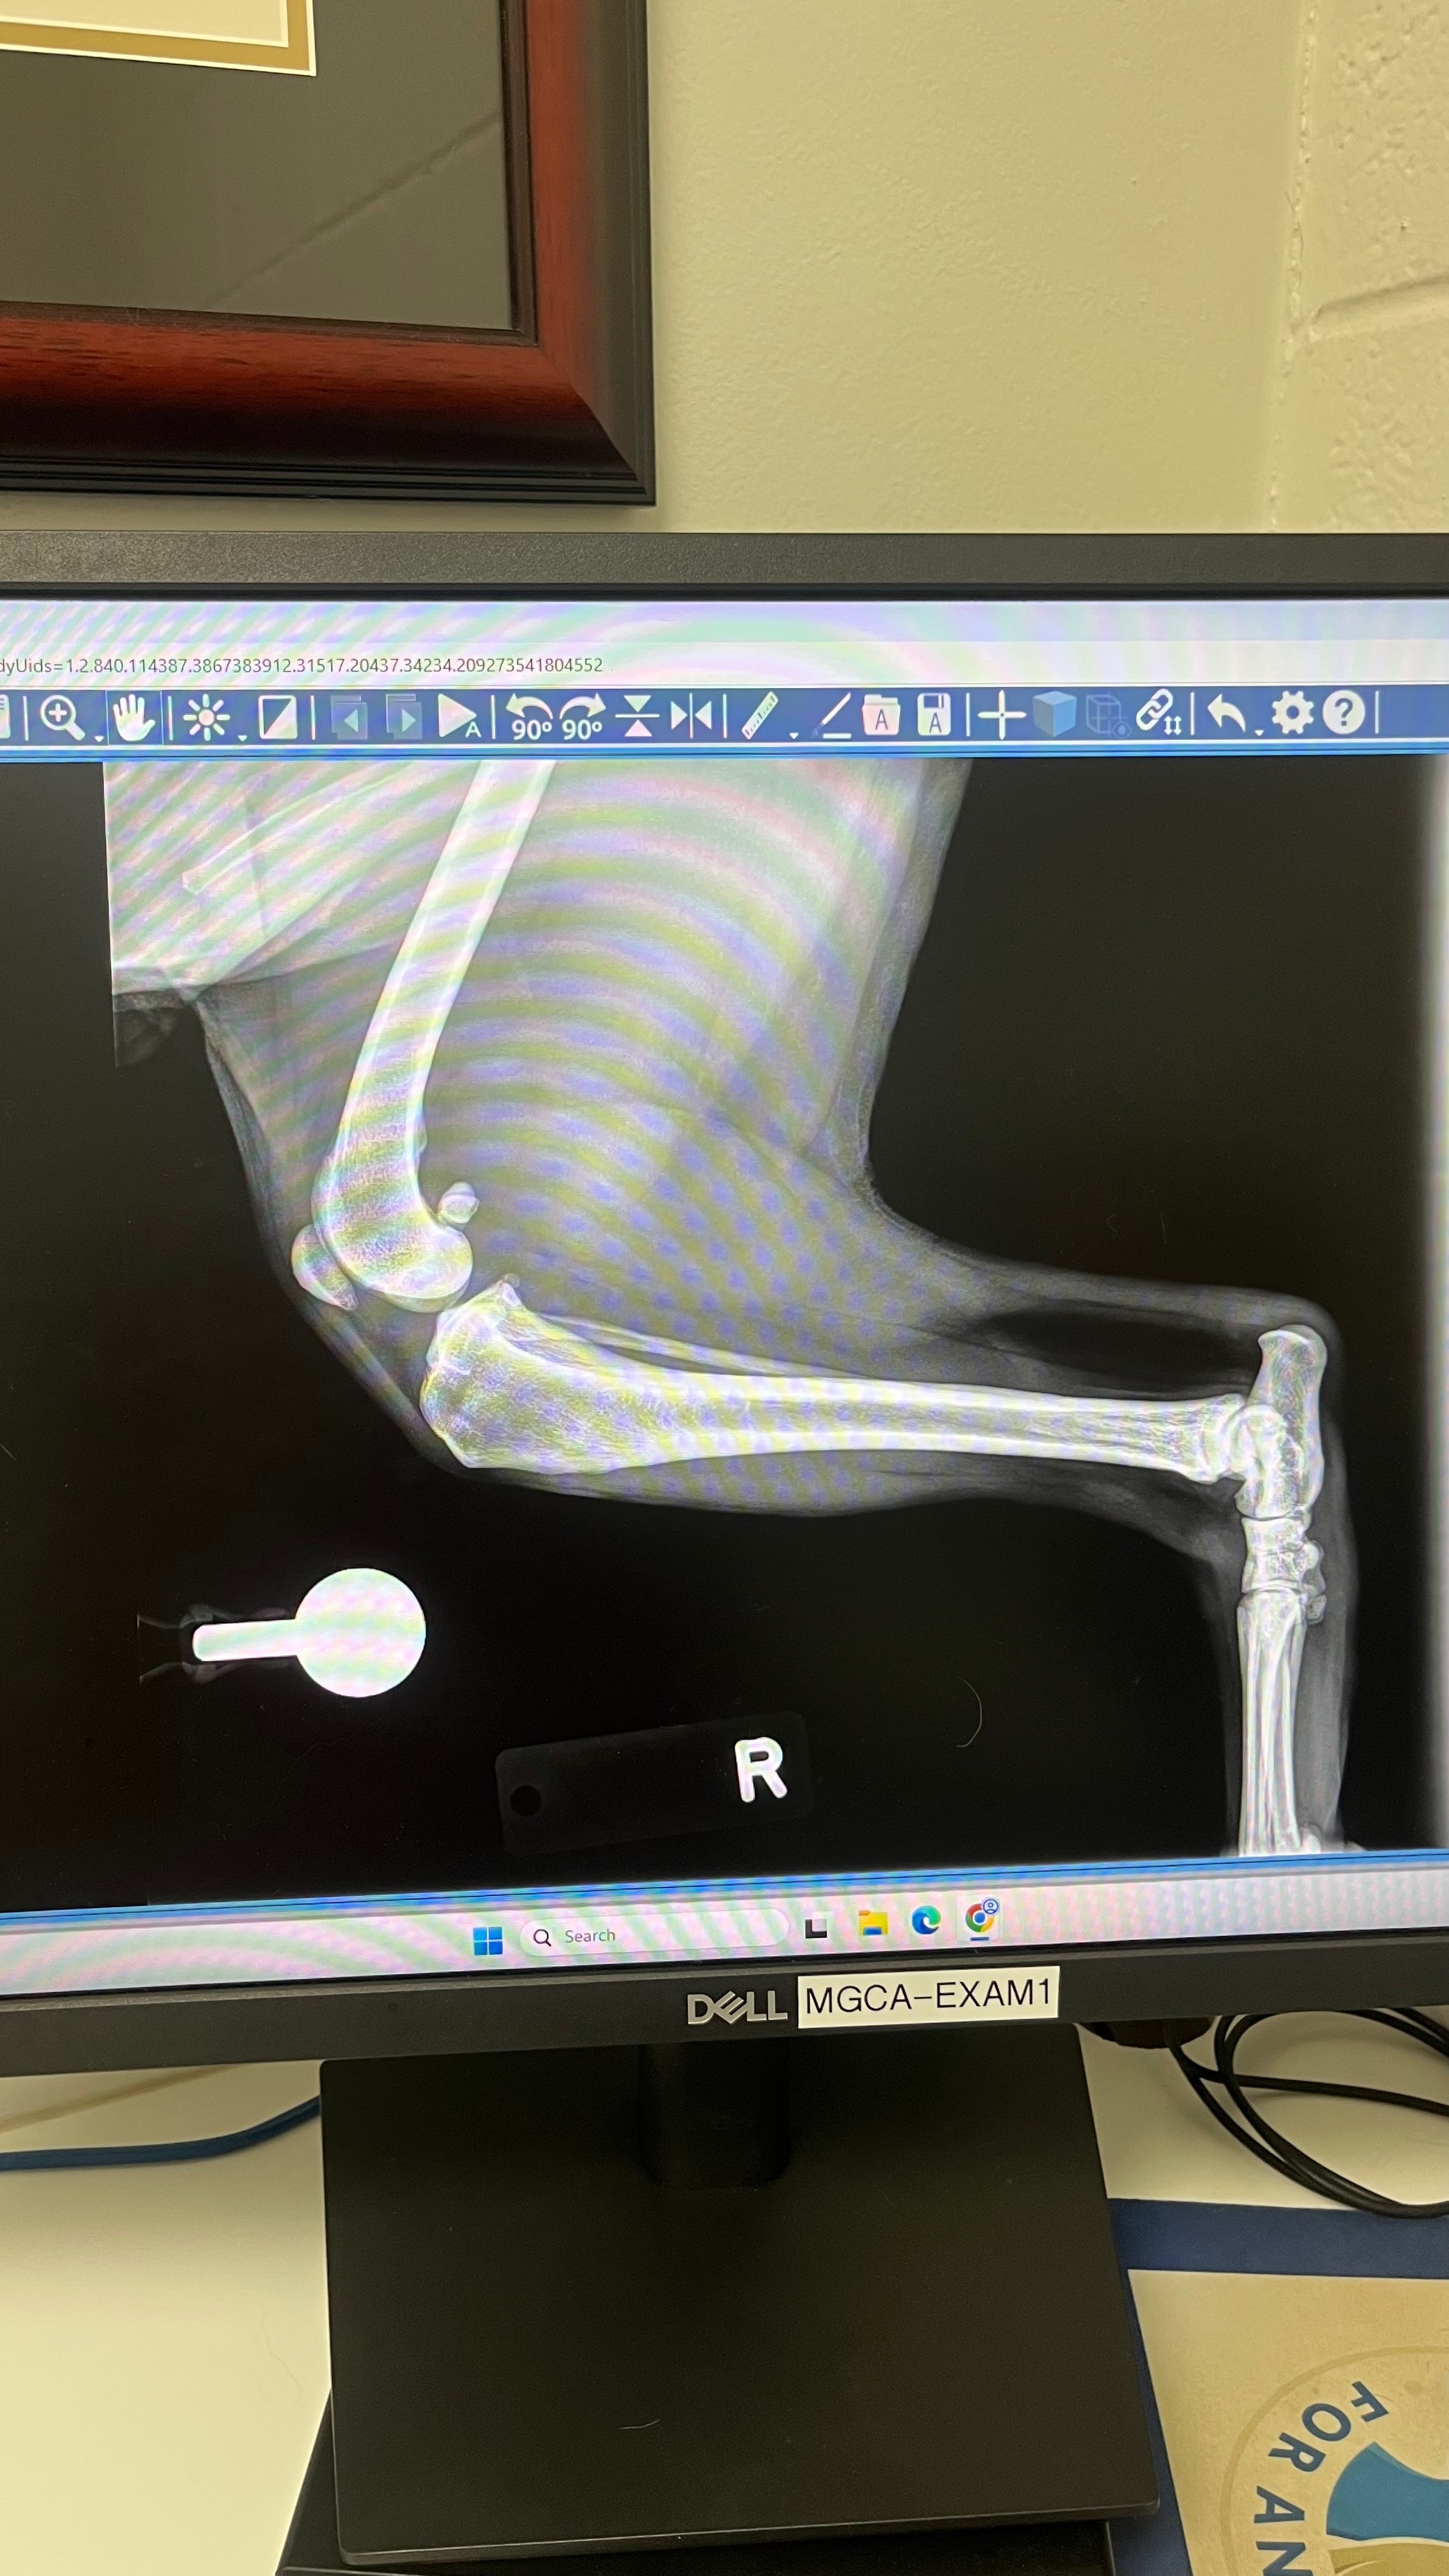

My dog Curly tore his ACL while playing in the yard. After receiving various veterinarian recommendations, the best option for him to heal and continue a happy life is surgery. Like any good pet owner, I want him to have the best surgery team and care and am asking for anyone who is able to support and donate during these hard times. Every donation will go toward Curly’s surgery and recovery care. Curly and I appreciate and are grateful for any support He has a tentative surgery date for Oct 29th.